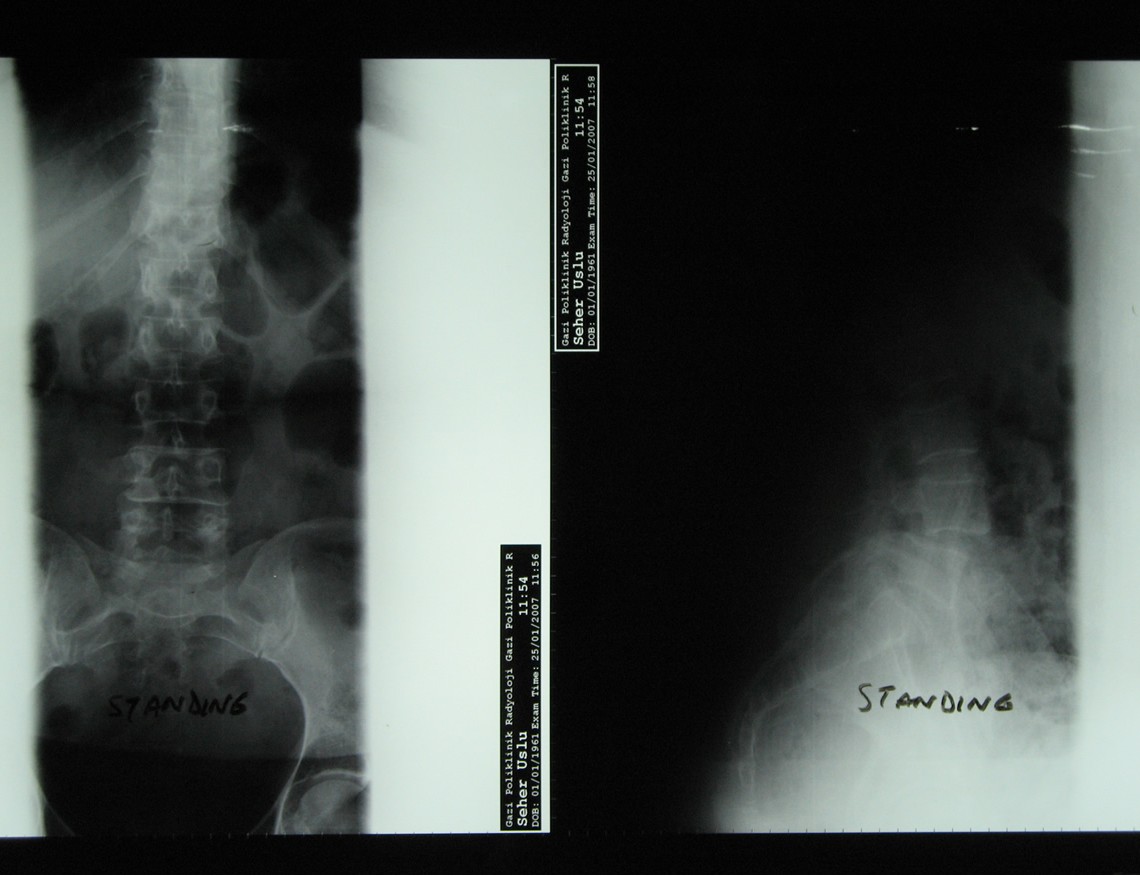

Bel kayması olan hastanın ameliyat öncesi ve sonrası röntgeni